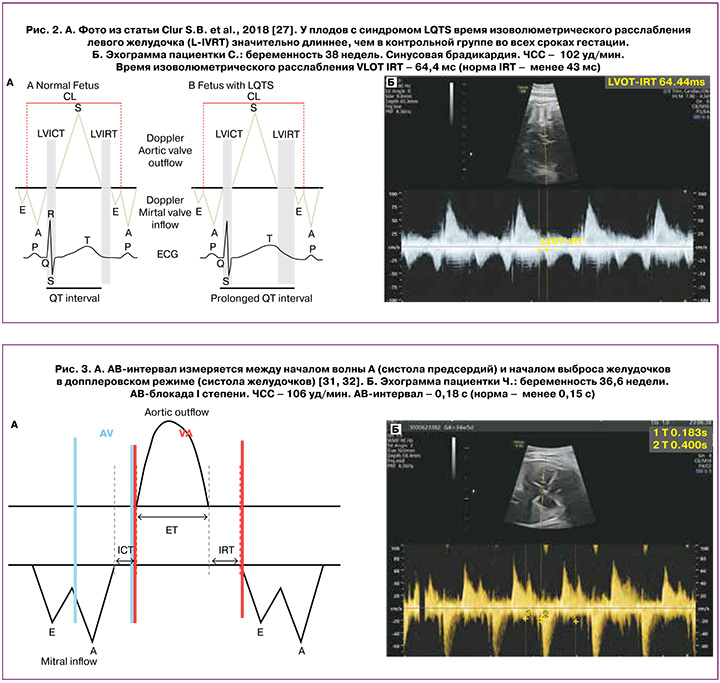

Согласно результатам исследований Clur S.B. et al. (2018), у плодов с синдромом LQTS время изоволюметрического расслабления левого желудочка (L-IVRT) значительно длиннее, чем в контрольной группе плодов с нормальным ритмом сердца во всех сроках гестации, и достоверно ассоциируется с удлинением интервала QT на постнатальной ЭКГ (рис. 2, а и б). Авторы пришли к выводу, что наряду с обнаружением синусовой брадикардии плода удлиненный показатель изоволюметрического расслабления левого желудочка (L-IVRT) может улучшить пренатальное выявление СУИQT [26].

Интервал PR – это время между систолой предсердий и систолой желудочков; у плодов известен как интервал времени АВ-сокращения (АВ-интервал) (рис. 3а). АВ-интервал получают в рамках одного сердечного цикла путем одновременного совмещения курсора синхронизированного импульсно-волнового допплера с притоком и оттоком левого желудочка (выводным трактом левого желудочка и митральным клапаном). Временной допплеровский интервал измеряется между началом волны А (систола предсердий) и началом выброса желудочков в допплеровском режиме (систола желудочков) [32, 33]. Нормальные значения АВ-интервала у плода составляют 0,12±0,02 с. Верхним пределом AВ-интервала считают 0,14 с, и 0,15 с рассматривают как 99-й процентиль для нормального диапазона на поздних сроках беременности [5] (рис. 3б).